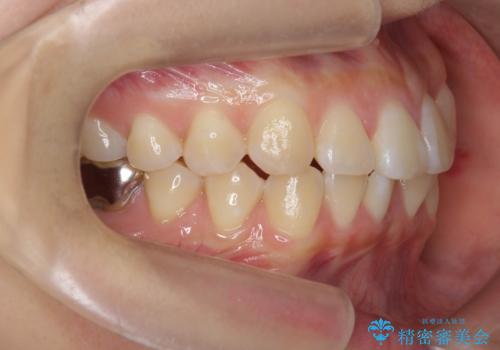

正中のズレ、引っ込んだ前歯の矯正

- 噛んだ時の前歯正中のズレ、引っ込んでいる前歯を治したい。と矯正治療を希望され来院されました。

左上2の前歯はスペースが足りないため、後方に引っ込んでしまっている状態です。

マウスピース矯正システムインビザラインで歯の後方移動、咬合関係の修正を行ったのち、引っ込んでいる左上2をワイヤーを用いて短時間で引き出す治療計画としました。

部分ワイヤー矯正を行なったことで約3ヶ月という短期間で前歯を綺麗に並べることができました。